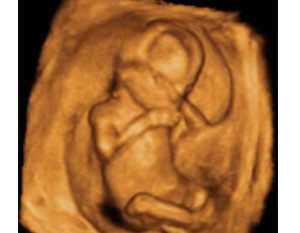

En la semana 16 en embarazo se producen muchos cambios en el bebé, que va adquiriendo un aspecto más humano: cejas, uñas, dedos de manos y pies, desarrollo de las extremidades…

Cómo es un bebé con 16 semanas de embarazo

- El feto mide entre 10,8 a 11,6 centímetros y pesa 80 gramos en la semana 16 de embarazo.

- Todo su cuerpo, incluida su cabeza, está recubierto de ese pelo tan fino, el lanugo, pero su apariencia se humaniza en esta fase de su desarrollo.

- Las primeras zonas en las que el bebé empieza a tener pelo son las cejas y sobre el labio superior. Tras el nacimiento, este pelo se cae y empieza a crecer otro más grueso que nace de nuevos folículos pilosos.

- También se forman las uñas de las manos y de los pies del bebé: se diferencian de los dedos.

- Las manos se abren y cierran, aunque lo normal es que éstas permanezcan cerradas y sólo se vean los dos puños en la ecografía de un feto de 16 semanas.

- Las piernas son más largas que los brazos y se mueven con mucha frecuencia. Se diferencian claramente rodillas, tobillos, codos y muñecas.